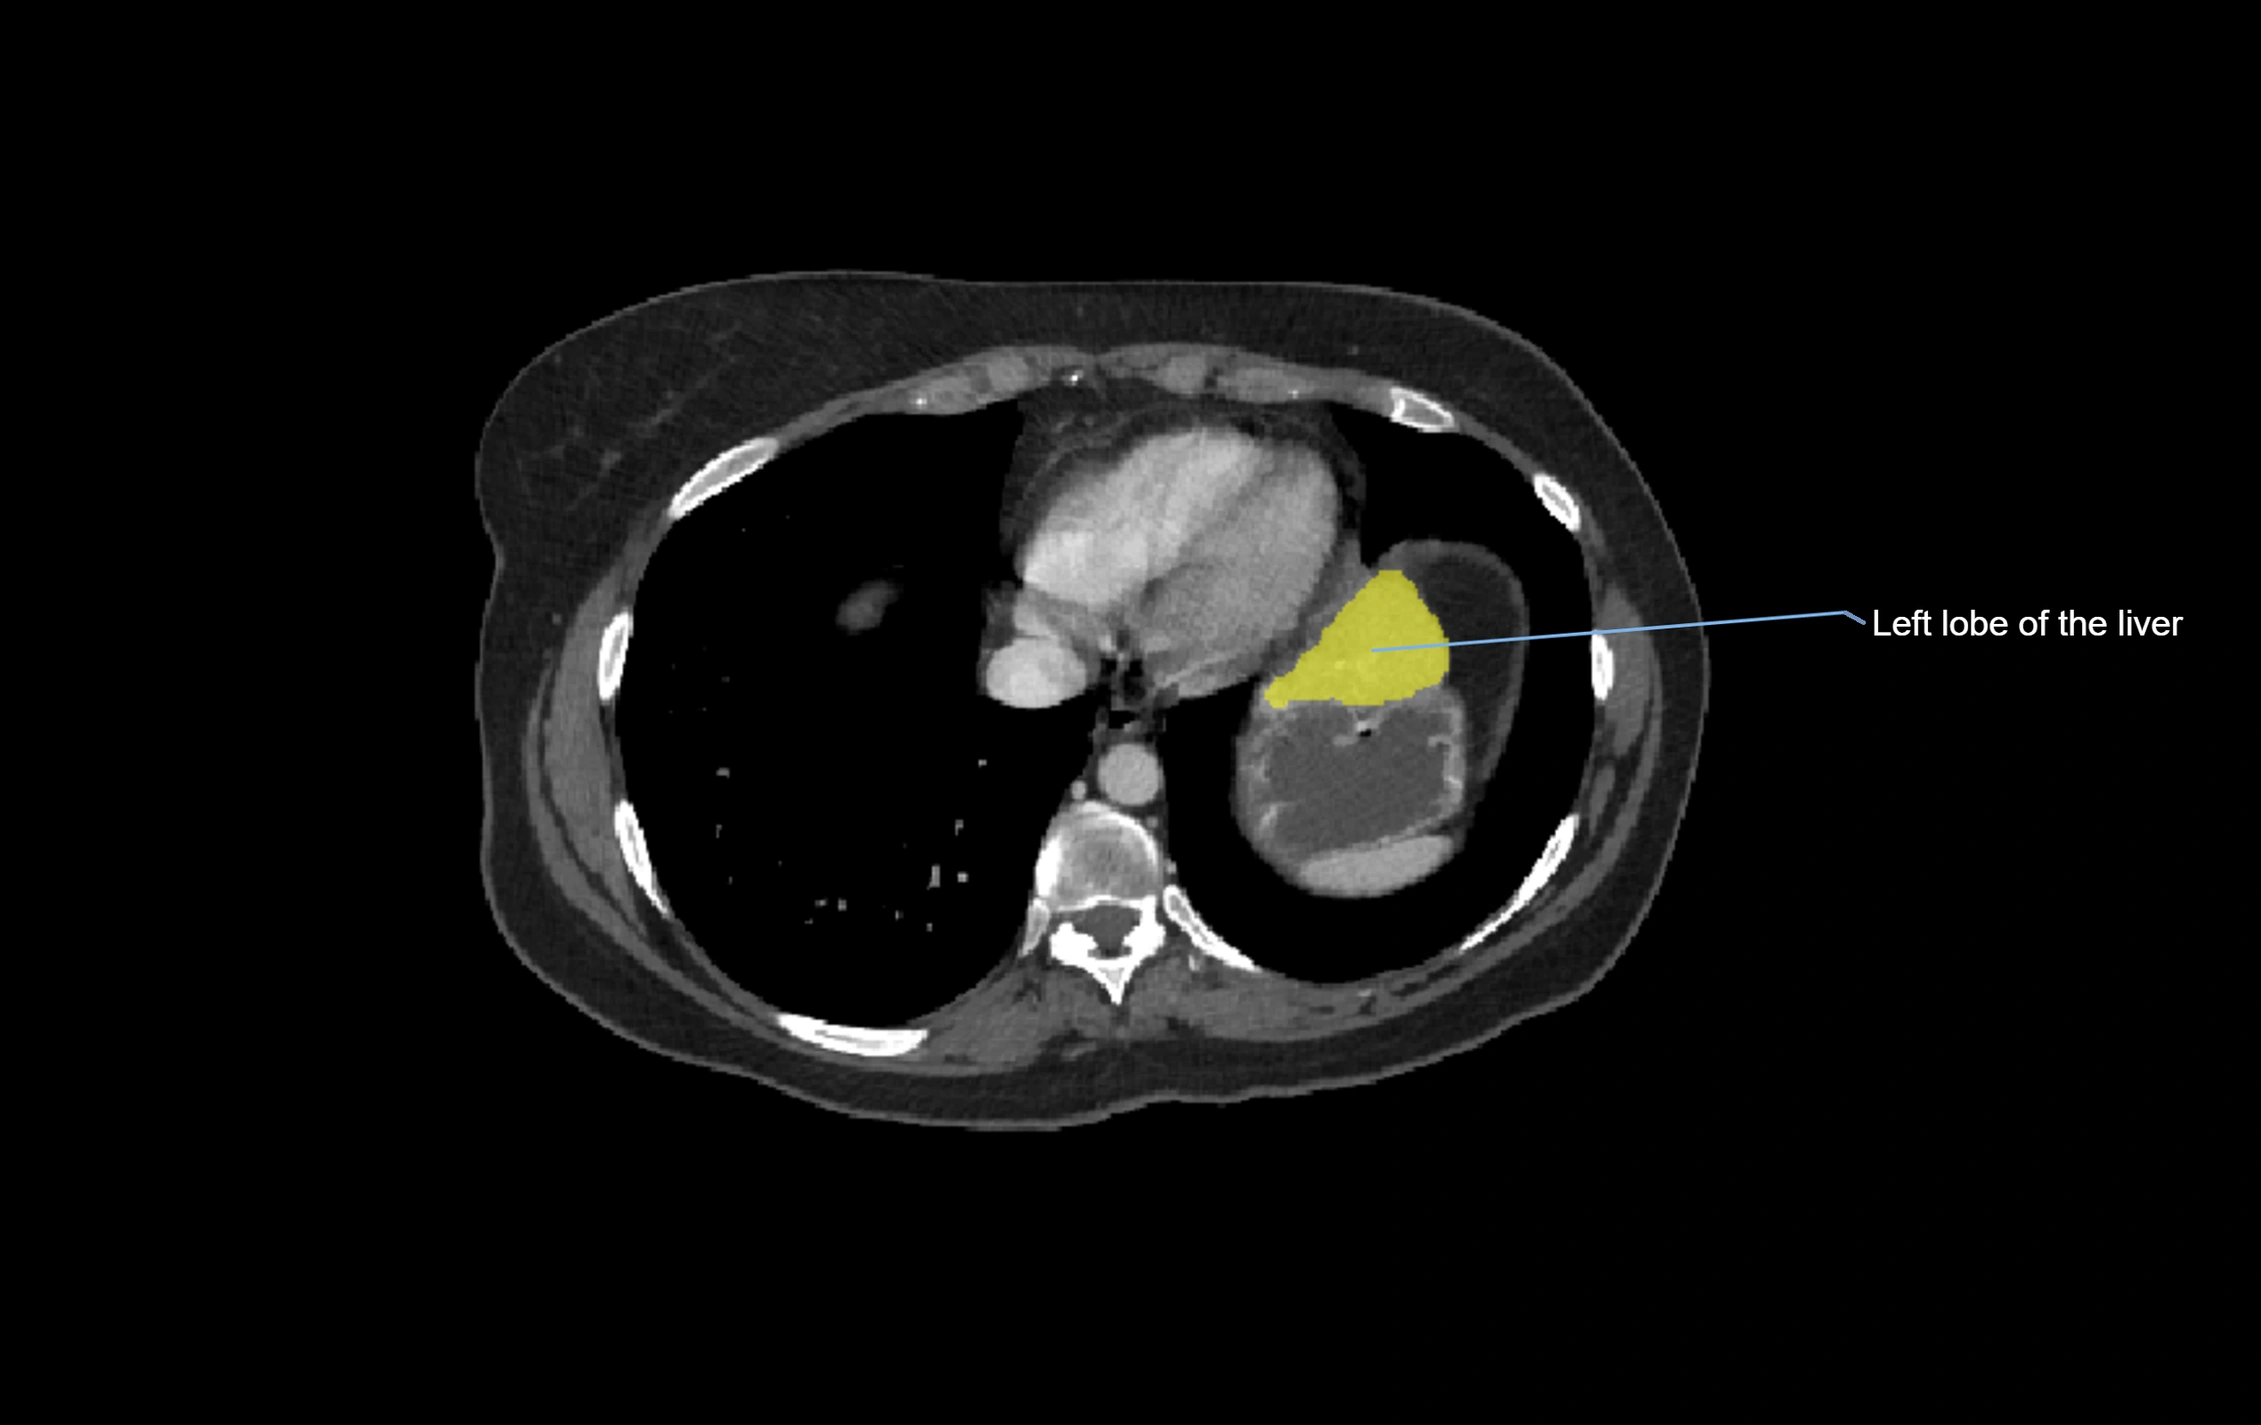

CT Image

image